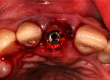

Anterior aesthetic zone implant placement and tooth restoration can be a quite challenging procedure. Modern technology offers new tools that can help maximize results in both aesthetic and functional ways. The socket-shield technique, as described by Hürzeler et al., boosted with the 3D diagnostics, digital planning, and 3D printing, could provide a valuable alternative to traditional approaches. This case report describes a clinical workflow for an efficient anterior implant-prosthetic restoration.